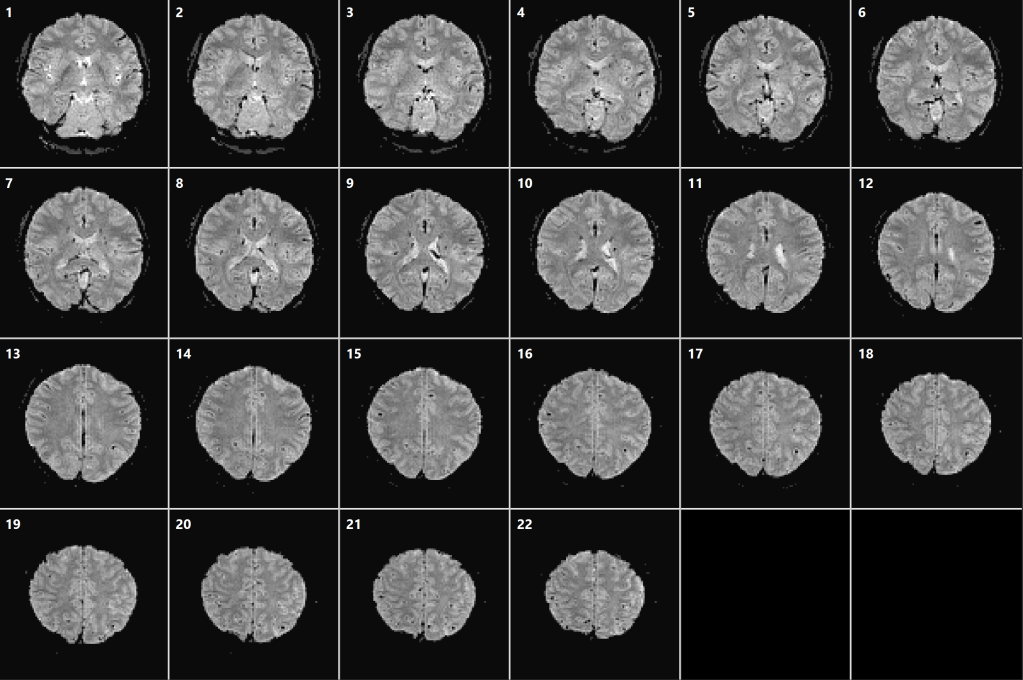

3T – fMRI